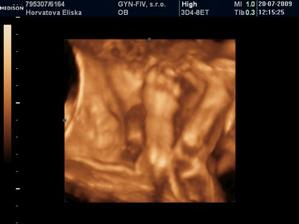

Dvojicky po KET

tak sme sa dockali-nase dvojicky sa narodili v 37+1 tt -20.10.09 cisarskym rezom -11:00 Matúško 3150g a 48cm a 11:02 Natálka 3030g 48cm,